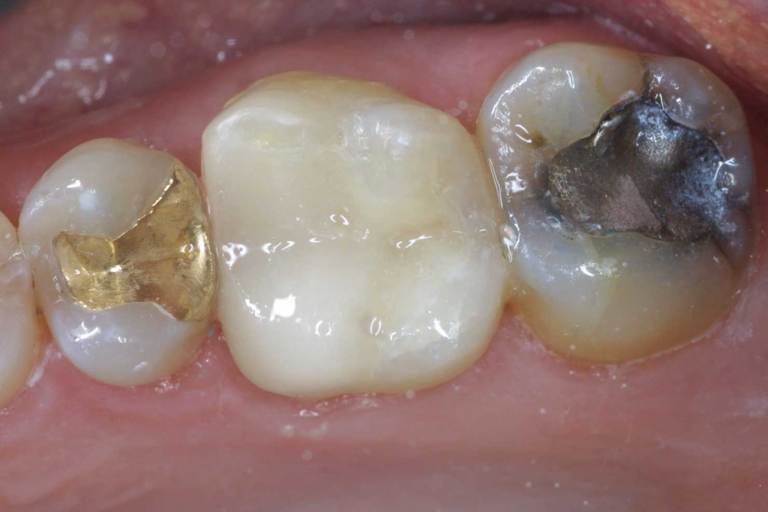

Tooth-colored fillings, white fillings and composite resin fillings are all names for the high-strength, natural-looking fillings that can be placed today instead of silver or gold (also known as amalgam fillings). No matter what the name, Implant and Family Dentistry will know just what you're talking about when referring to this natural-looking filling.

Composite fillings are today's modern filling choice. They are made to match your tooth's natural color to make them virtually invisible to notice and are placed onto the tooth by bonding the filling material to the tooth so they do not have the unlikely chance of falling off. Many patients choose to replace their old silver and gold fillings with composite fillings.

There is now new technology that allows you to replace old silver and gold fillings with a more natural looking, composite filling. Composite fillings are bonded to the tooth and research has proven them to be about 90% as strong and healthy as natural tooth material.